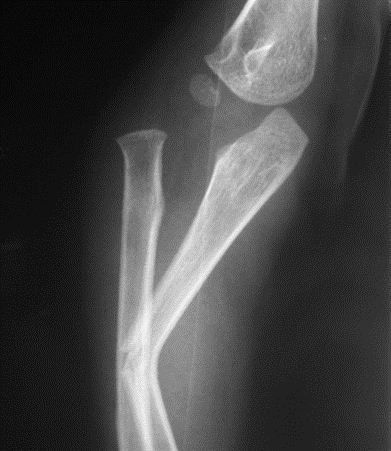

Cẳng tay gồm có 2 xương: Xương quay và xương trụ. Gãy trật Monteggia là gãy thân xương trụ và trật khớp quay trụ trên và một phần cấu trúc khớp khuỷu. Gãy trật Monteggia là một trong những tổn thương không thường gặp trong bệnh lý chấn thương ở trẻ em, việc chẩn đoán và điều trị sớm mang lại những kết quả tốt.

Chẩn đoán hình ảnh dựa vào XQ khuỷu thẳng và nghiêng khi trục xương quay không đi qua tâm chỏm con xương cánh tay.

Điều trị gãy Monteggia ở trẻ em đến sớm chủ yếu là nắn chỉnh bất động bột. Phương pháp này có thể thực hiện ở các cơ sở y tế, mang lại hiệu quả. Thông thường khi điều trị xương trụ về đúng giải phẫu, đài quay cũng sẽ về đúng vị trí, bất động bột được duy trì khoảng 4 – 6 tuần rồi tập luyện phục hồi chức năng gấp – duỗi khuỷu, sấp ngửa cẳng tay.